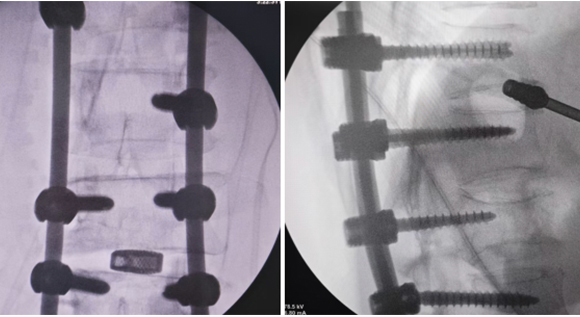

• 5脊柱骨折+腰椎滑脱-椎弓根钉内固定术